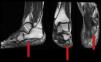

Ante la sospecha de afección no inflamatoria, y con la radiografía donde se aprecia entesofito calcáneo, se solicitó RMN, que mostró una importante atrofia con reemplazamiento graso del músculo abductor del quinto dedo, y múltiples venas dilatadas o varicosidades en la cara interna del pie en el recorrido del nervio calcáneo inferior (fig. 1), compatibles con neuropatía compresiva de Baxter.